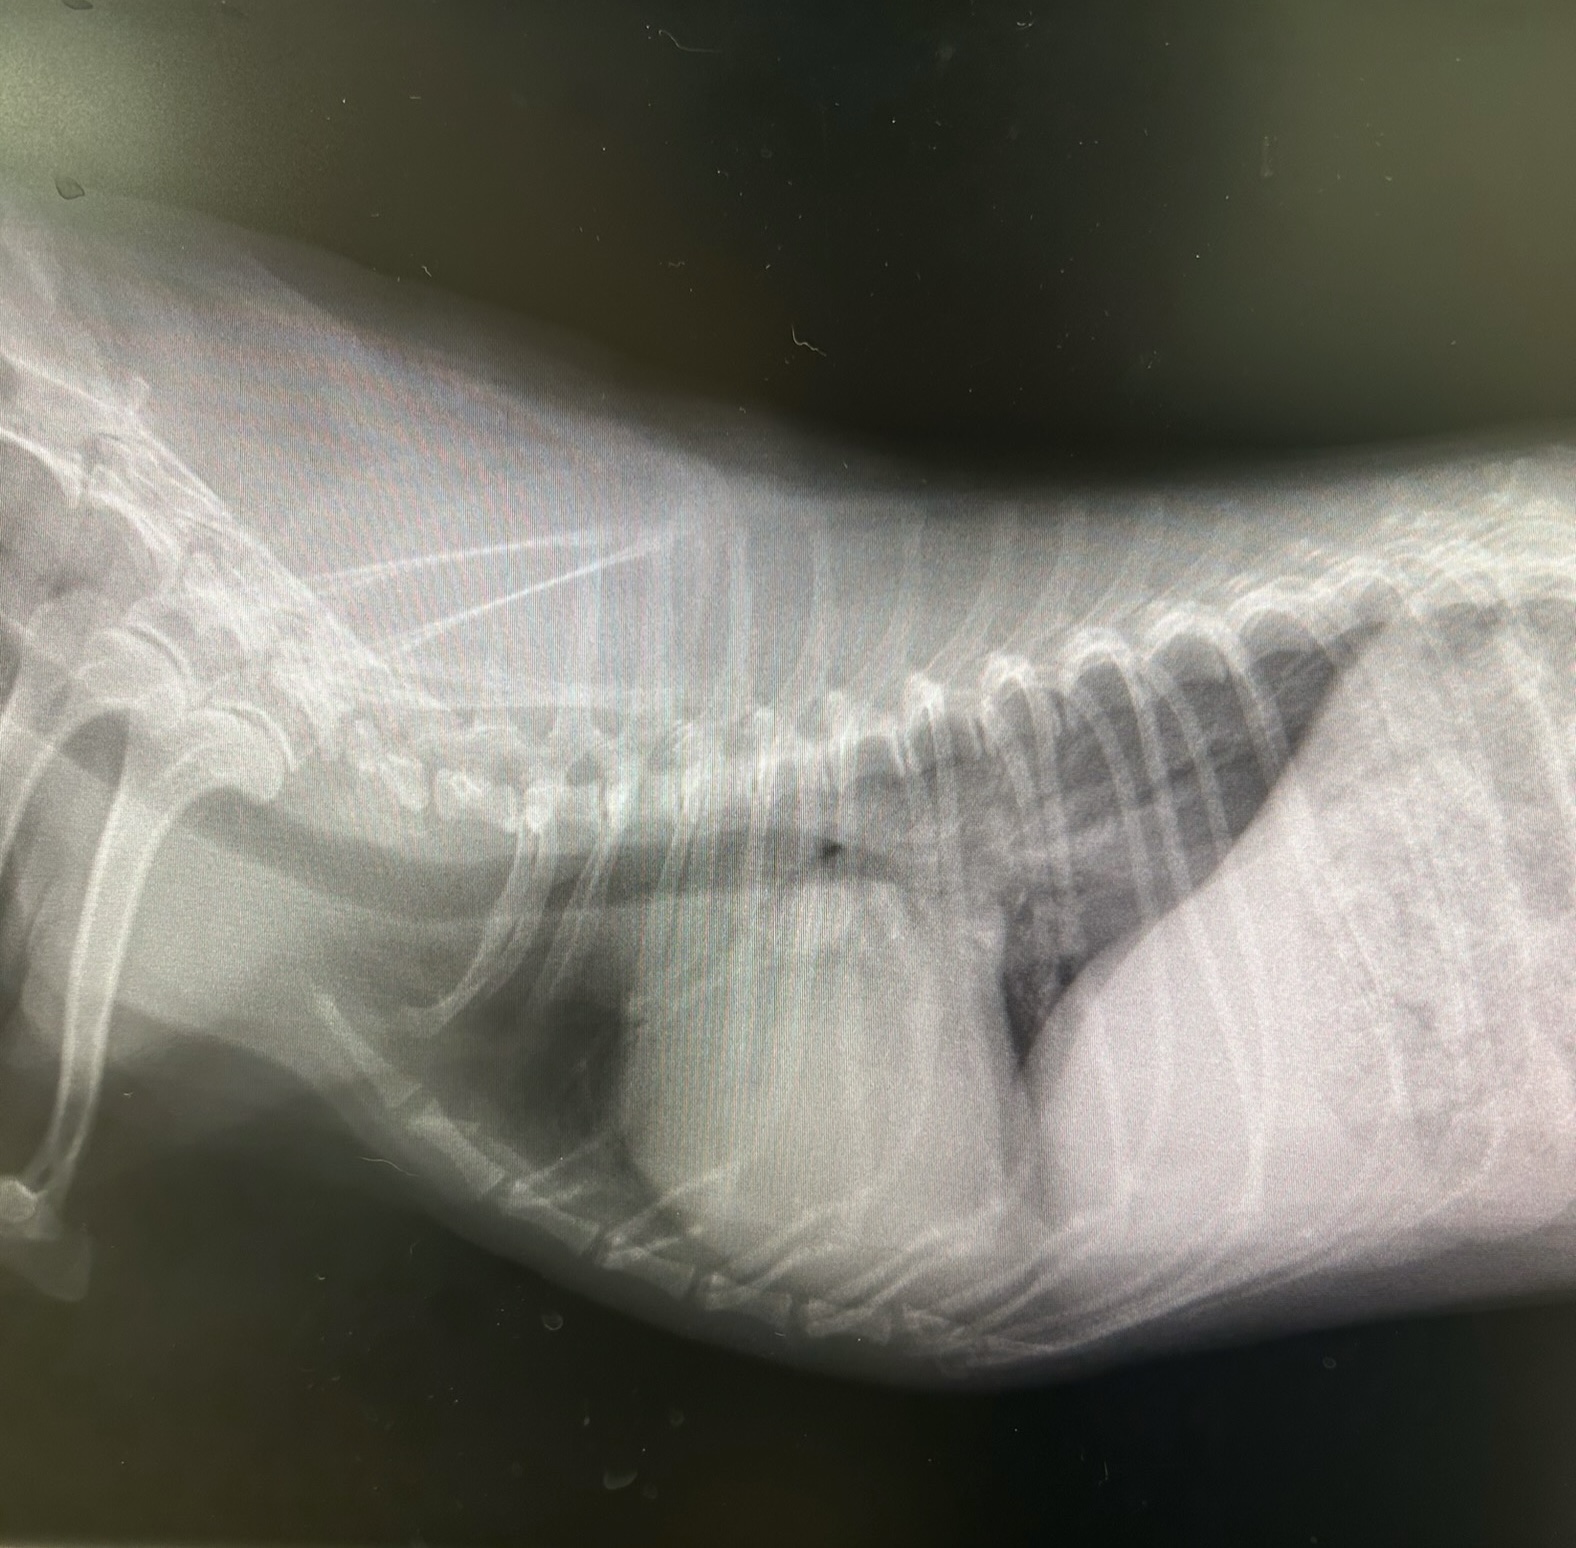

3. X線検査: 心臓に負担がかかって、心拡大が起きていないか調べられます。また、『肺水腫』が起きているかどうかもわかります。

治療前の写真